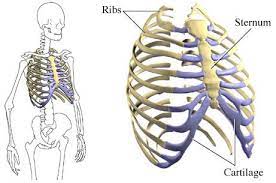

قیمت: 118٬000 تومان - دسته بندی فایل: پاورپوینتپاورپوینت آناتومی سیستماتیک ستون مهره ها دنده ها و جناغ

فروش ویژه پاورپوینت حرفه ای آناتومی سیستماتیک ستون مهره ها دنده ها و جناغ با تخفیف استثنایی فقط 113 هزار تومان تعداد اسلاید: 89 اسلاید